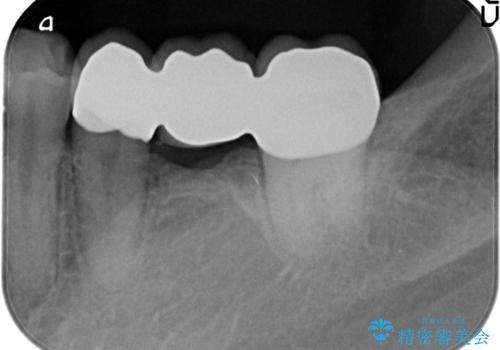

今回はブリッジでの補綴を希望されたため、オールセラミッククラウンにより治療を行っております。

今回は両隣在歯に修復治療が行われており、外科治療を伴わないブリッジにて修復を希望され治療を行っております。